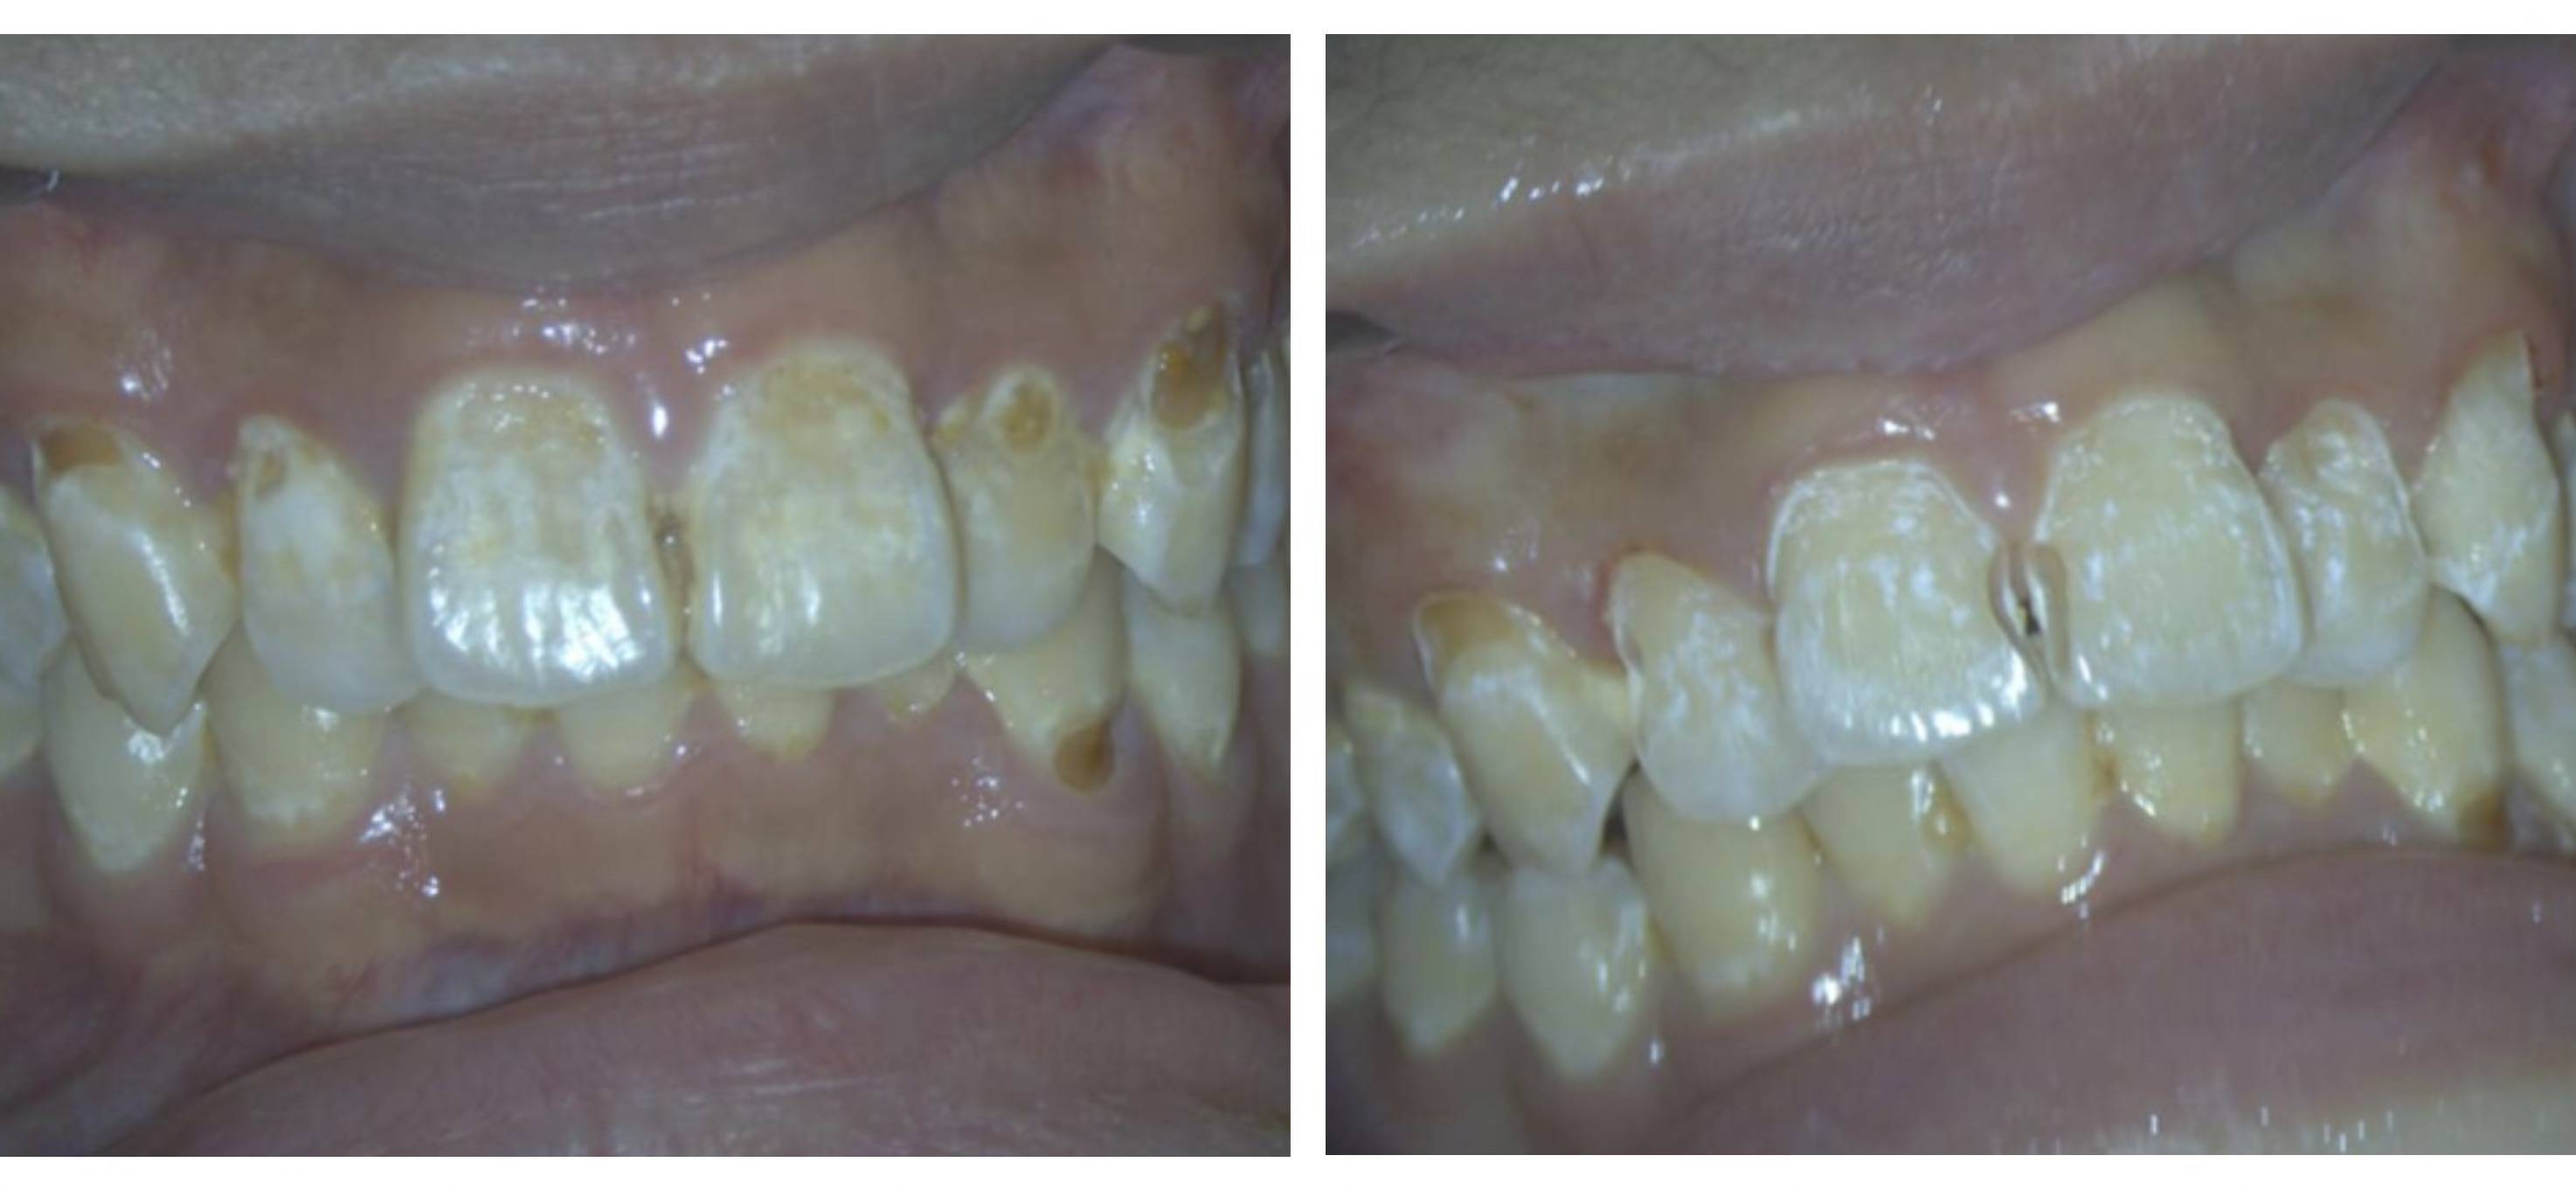

“孩子前面牙齿黄一块、白一块,看着也不像一般的蛀牙,不知道怎么回事?”近日,13岁的小飞(化姓)在家人的陪同下前往东南大学附属中大医院口腔科就诊。陈耀忠主任检查发现,患者前牙唇面颈部已经出现不同程度的龋坏、白垩色斑块等脱矿改变,病变范围广,累及牙齿多,确诊为猛性龋。问诊中发现,小飞还是饮料“酷爱”者。

多颗牙齿龋坏

其家人无奈表示,孩子平时不是喝可乐、果汁等含糖饮料,就是喝酸奶、牛奶,几乎很少喝白开水。“可乐、果汁等饮料中富含糖及酸,口腔中的细菌可以利用粘附于牙齿表面的糖产酸,从而造成溶解牙齿中的钙、磷,造成牙齿脱矿、龋坏。”陈主任一边解释,一边为患者去除龋坏组织,经过酸蚀、树脂充填、精修抛光等治疗,小飞的“门面”终于亮堂了。万幸的是,因为发现得早,并未龋坏到牙髓。